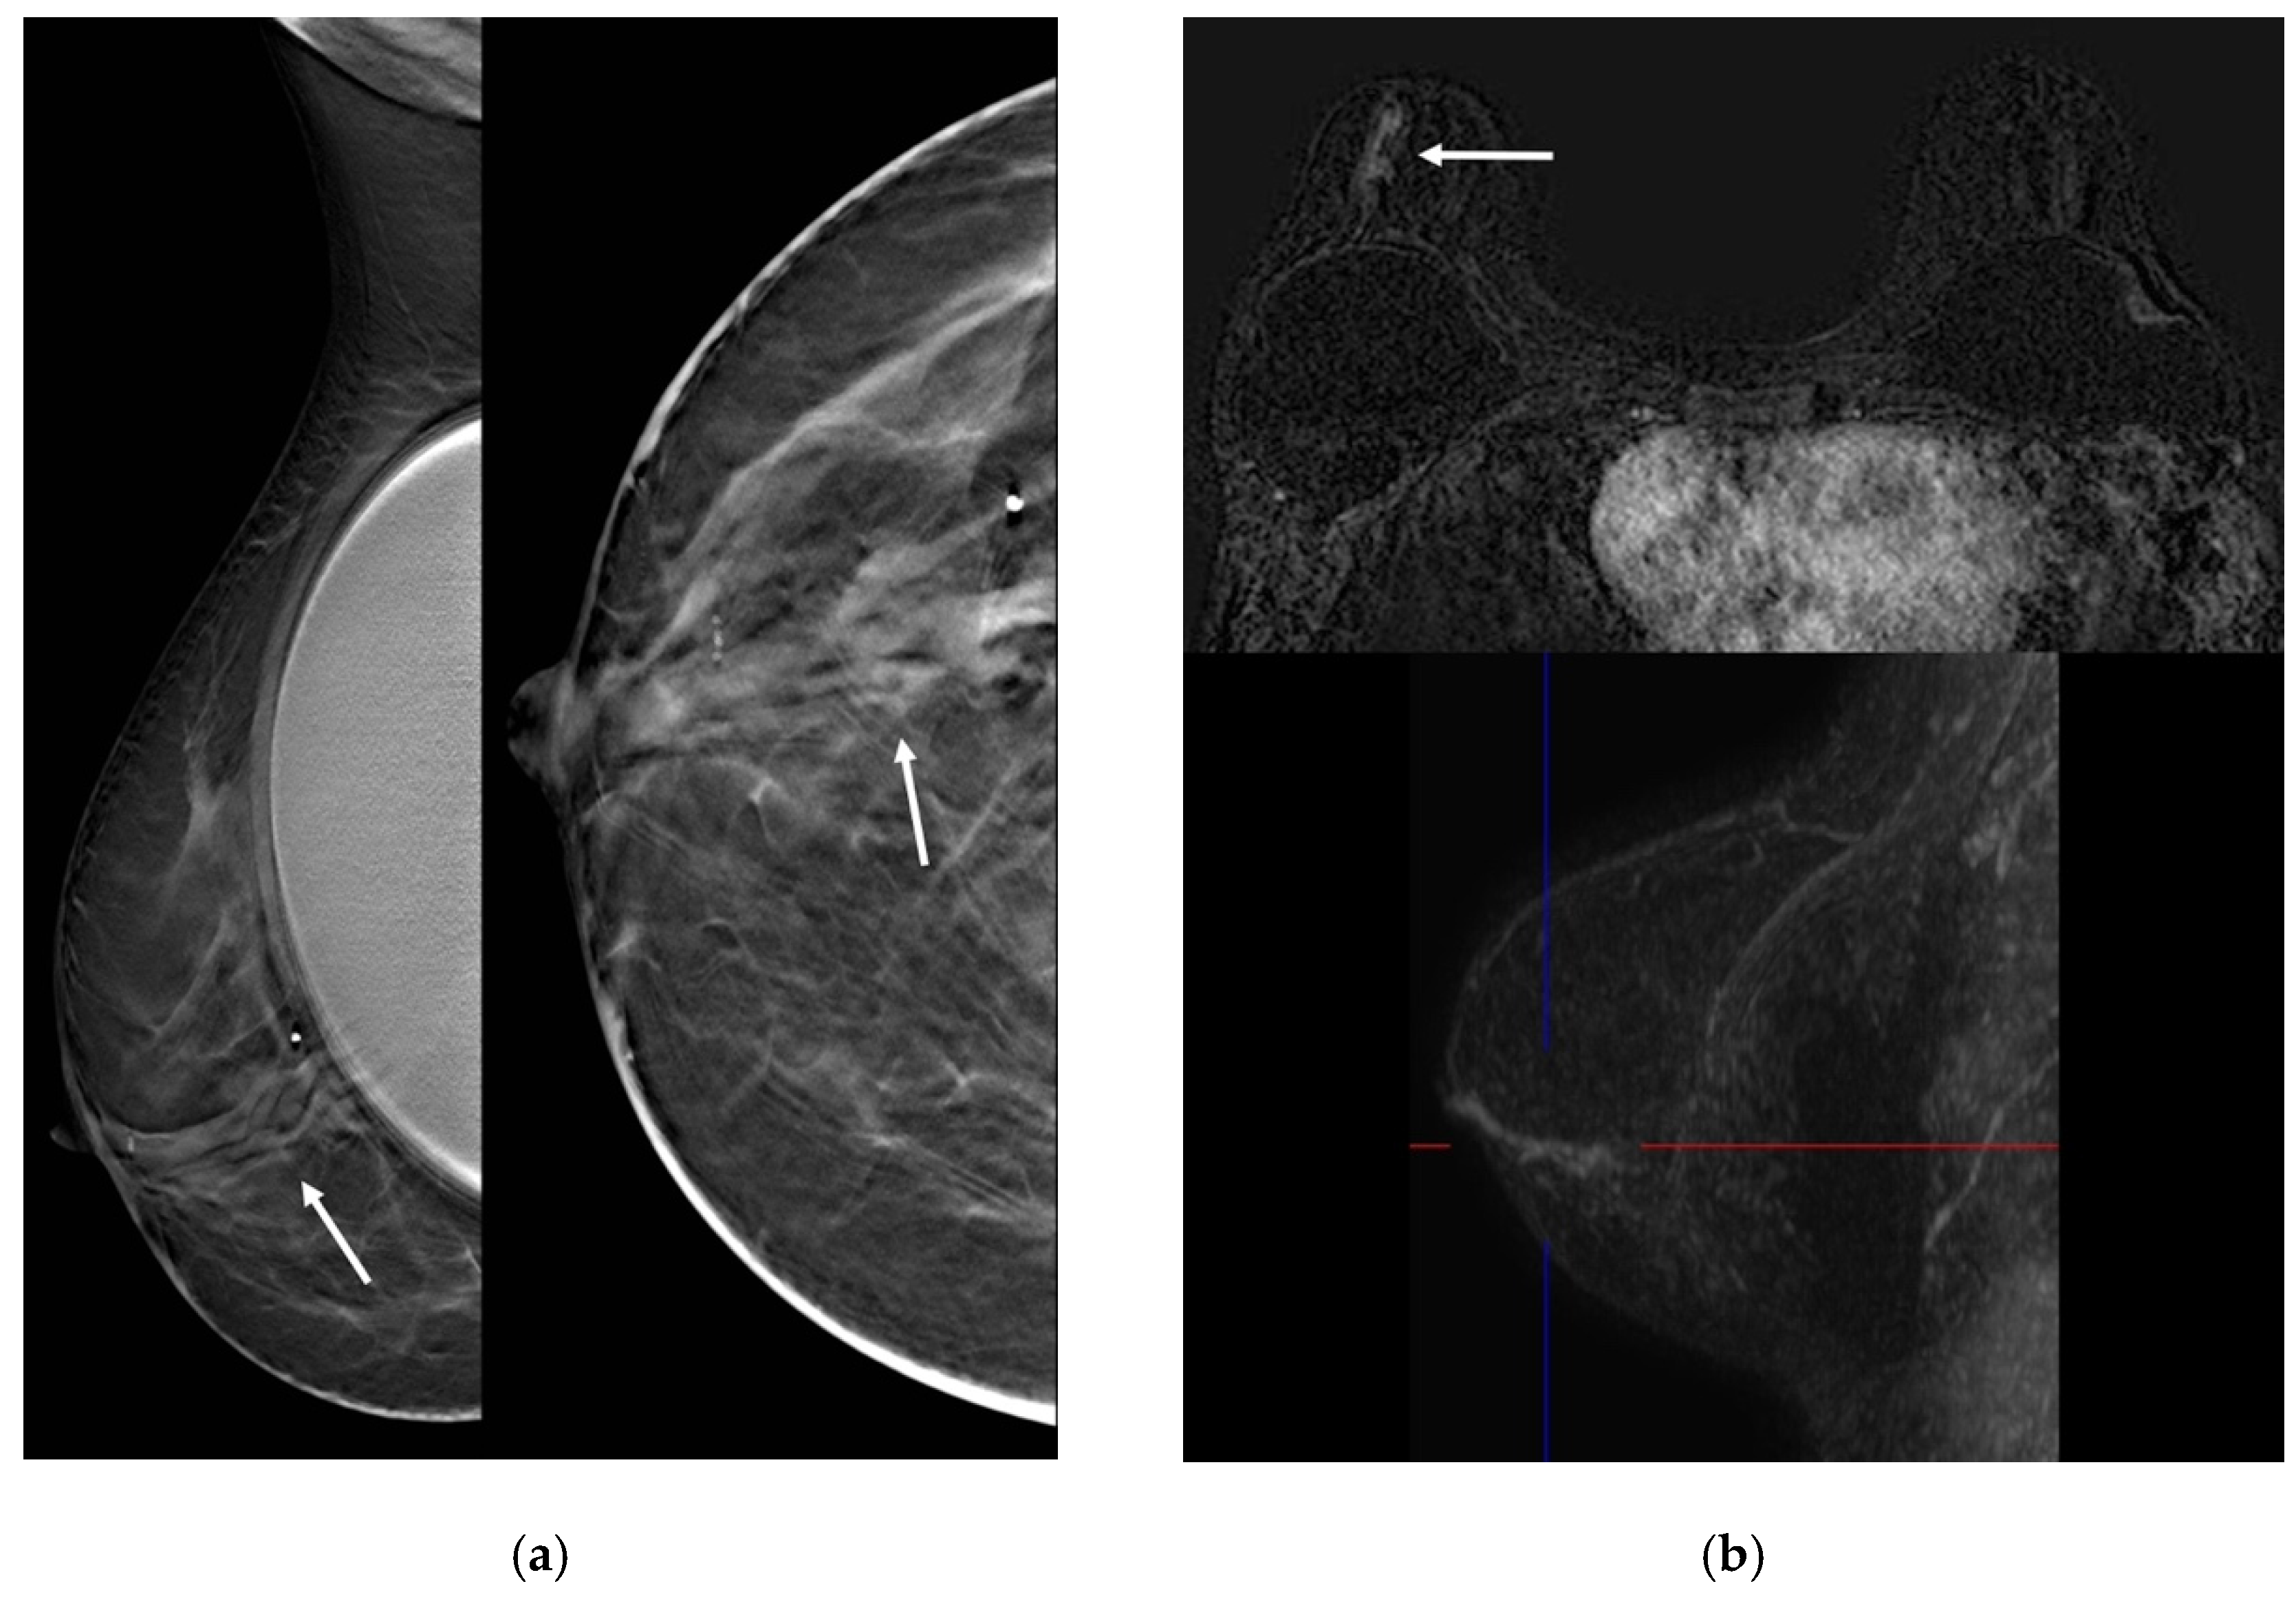

| Son 2009 [25] | Retrospective cohort, patients who underwent surgery due to papillomas of the breast and performed 3D fast low-angle shot (FLASH) dynamic breast MRI | NR | 3 | 41.7 ± 12.9 (27–51) | 2/3 palpable mass, 1/3 bloody nipple discharge | MX: 2/3 microcalcifications US: 3/3 multiple masses MRI: 1/3 multiple nodular enhancement; 1 ductal non-mass enhancement, 1 segmental non-mass enhancement | NR | NR | NR | |

| Sarica 2018 [26] | Retrospective cohort, patients with a pathologic diagnosis of papillary lesion who performed MRI and US | NR | 11 | 41.45 ± 7.7 | 1/11 palpable mass, 3/11 unilateral nipple discharge | US: 3/11 dilated duct partially/completely filled with intraluminal content; 1/11 mass with ductal relation or intracystic mass; 6/11 heterogeneous tubular nonmass-like hypoechoic area or mass related to multiple dilated ducts; 1/11 occult MRI: 3/11 dilated duct and intraductal focal mass on T2; 2/11 Dilated duct and pre-contrast high T1 signal; 2/11 mass with crescentic peripheral fluid; 3/11 mass related with dilated duct-ductal contrast enhancement; 1/11 linear-ductal contrast enhancement; 3/11 segmental contrast enhancement | NR | NR | NR | |